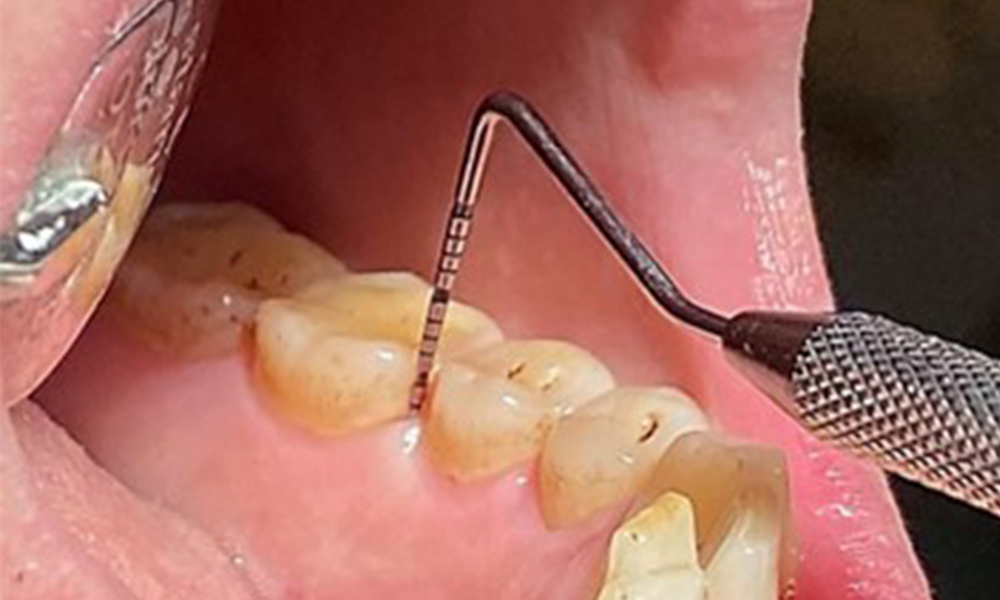

Aufgrund des guten allgemeinmedizinischen Zustandes ist der aus der Mundgesundheit ermittelte Bedarf maßgebend für die Behandlung. Die regelmäßige Erhebung der Sondierungstiefen ist unabdingbar. Die gingivale Blutung ist bei Rauchern herabgesetzt, weswegen die klinische

Diagnose einer Parodontitis nur durch Sondierung möglich ist (Abb. 7). Die ausschließliche Erhebung von Blutungsindizes verdecken unter Umständen das Bild einer bestehenden Parodontitis oder Gingivitis. (5)

Taschensondierung (BOP) mit Darstellung der Rg. 36 lingual

Abb. 7 Taschensondierung (BOP) mit Darstellung der Rg. 36 lingual, © Dr. R. Krapf